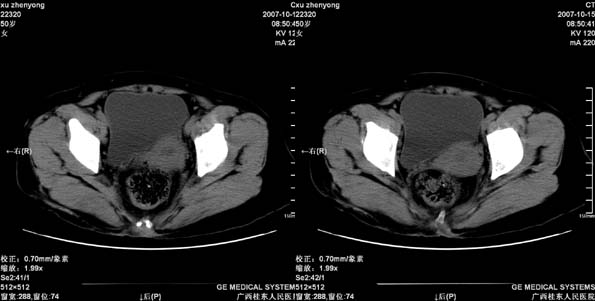

患者,女 50岁.会阴部坠胀感一月余,有痔疮病史,近期有便血;患者今年5月分结肠镜检查未见异常(由于患者不愿意ct增强扫描)没做增强,现准备手术,请各位老师会诊.

偏侧直肠壁增厚,支持直肠癌,不除外内痔.

直肠下端及肛门周围可见软组织改变,如果5月份检查的结肠镜结果可靠,那么本病例痔的可能性还是很大的。肿瘤生长的不会如此之快。

直肠左侧壁明显增厚,考虑直肠癌可能性大.